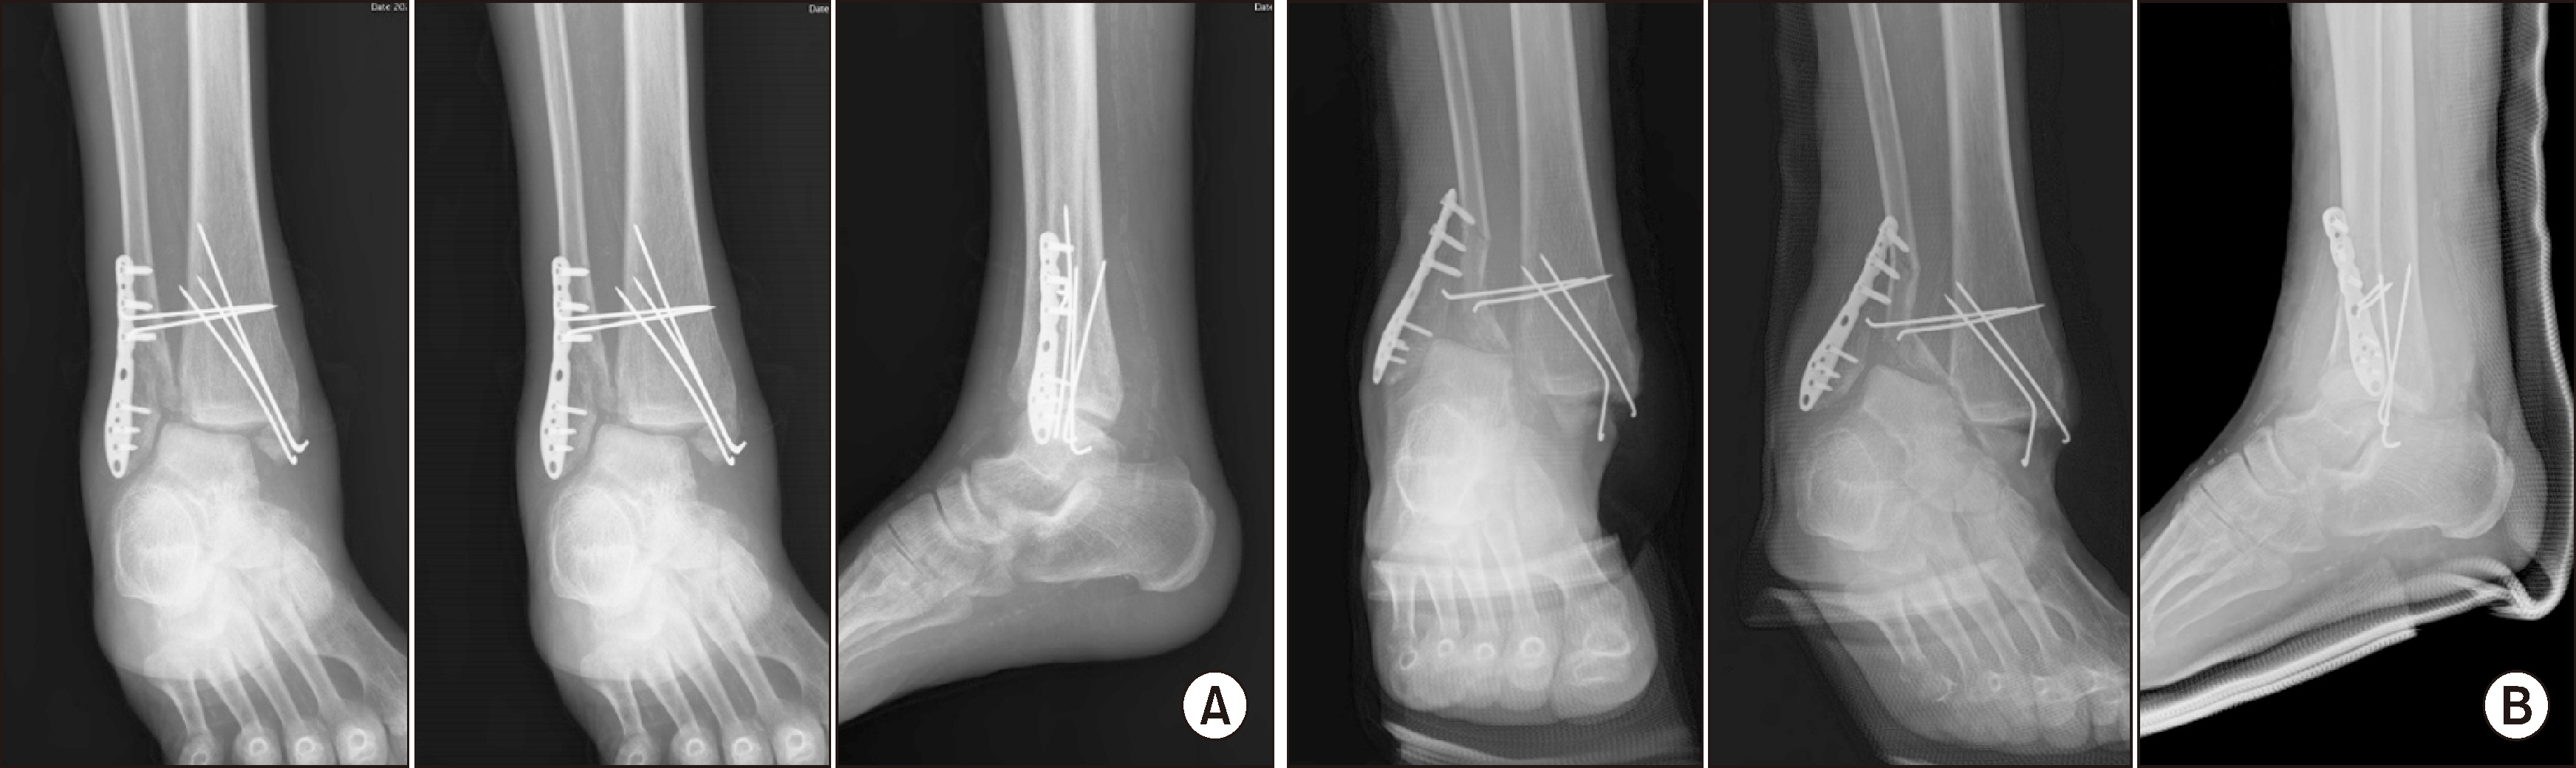

Comprehensive Management of Presumed Underlying Charcot Arthropathy with a Subsequent Traumatic Ankle Fracture in a Patient with Diabetes Mellitus, End-Stage Renal Disease: A Case Report

Charcot neuroarthropathy (CN), also known as Charcot arthropathy, is a complex, progressive disorder primarily affecting the foot and ankle. This case report describes a multifaceted management strategy for a 54-year-old male with diabetes mellitus, end-stage renal disease, and presumed underlying Charcot arthropathy who experienced a traumatic ankle fracture. The initial surgical plans were delayed because of systemic infection indicators, including elevated C-reactive protein levels and high fever. The patient underwent multiple surgical interventions and faced challenges, including metal failure, implant-associated infection, and tibiotalar joint dislocation. A multidisciplinary approach involving orthopedic surgeons, nephrologists, and endocrinologists was crucial for managing the case effectively. In particular, the patient declined a below-knee amputation and opted for comprehensive surgical intervention, resulting in improved functionality at the latest follow-up. This case highlights the complexities of managing CN in patients with multiple comorbidities and emphasizes the need for a nuanced, patient-centered approach.